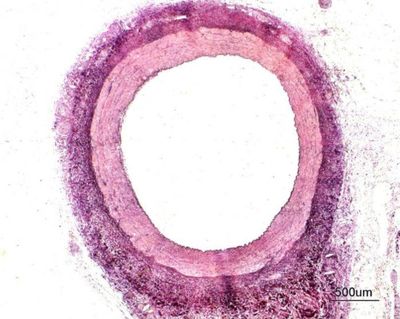

-Con respecto a la constitucion de Arterias elasticas:

Las células que encontramos en la capa adventicia son mayoritariamente fibroblastos y macrófagos.